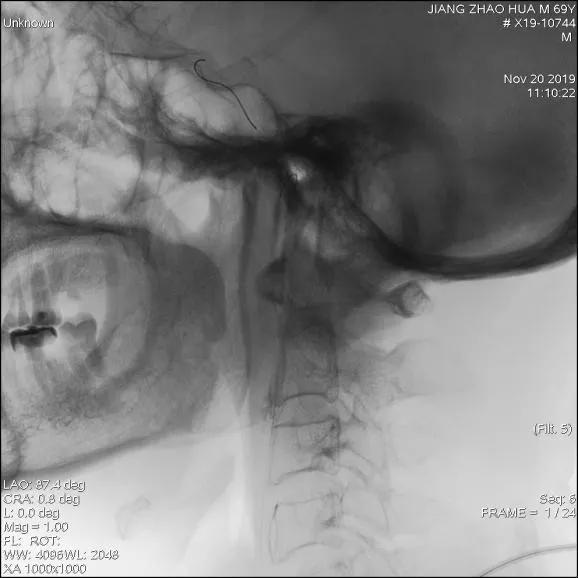

患者取仰卧位,常规消毒铺巾,Seldinger技术穿刺右股动脉,置入股鞘,引入8F导引导管至左侧颈总动脉分叉近端,造影提示:左侧颈内动脉近段肿瘤侵犯至狭窄,长约15mm,远端走形正常;后引入FilterWire EZ保护伞顺利通过狭窄段至C1远端,释放保护伞;引入4.5mm*16mm WILLIS®覆膜支架,精准定位后,缓慢球囊扩张释放支架。

支架展开,造影图示狭窄消失

全脑血管造影图

造影图提示:支架位置佳,膨胀好,未见内漏,原狭窄段基本恢复正常。